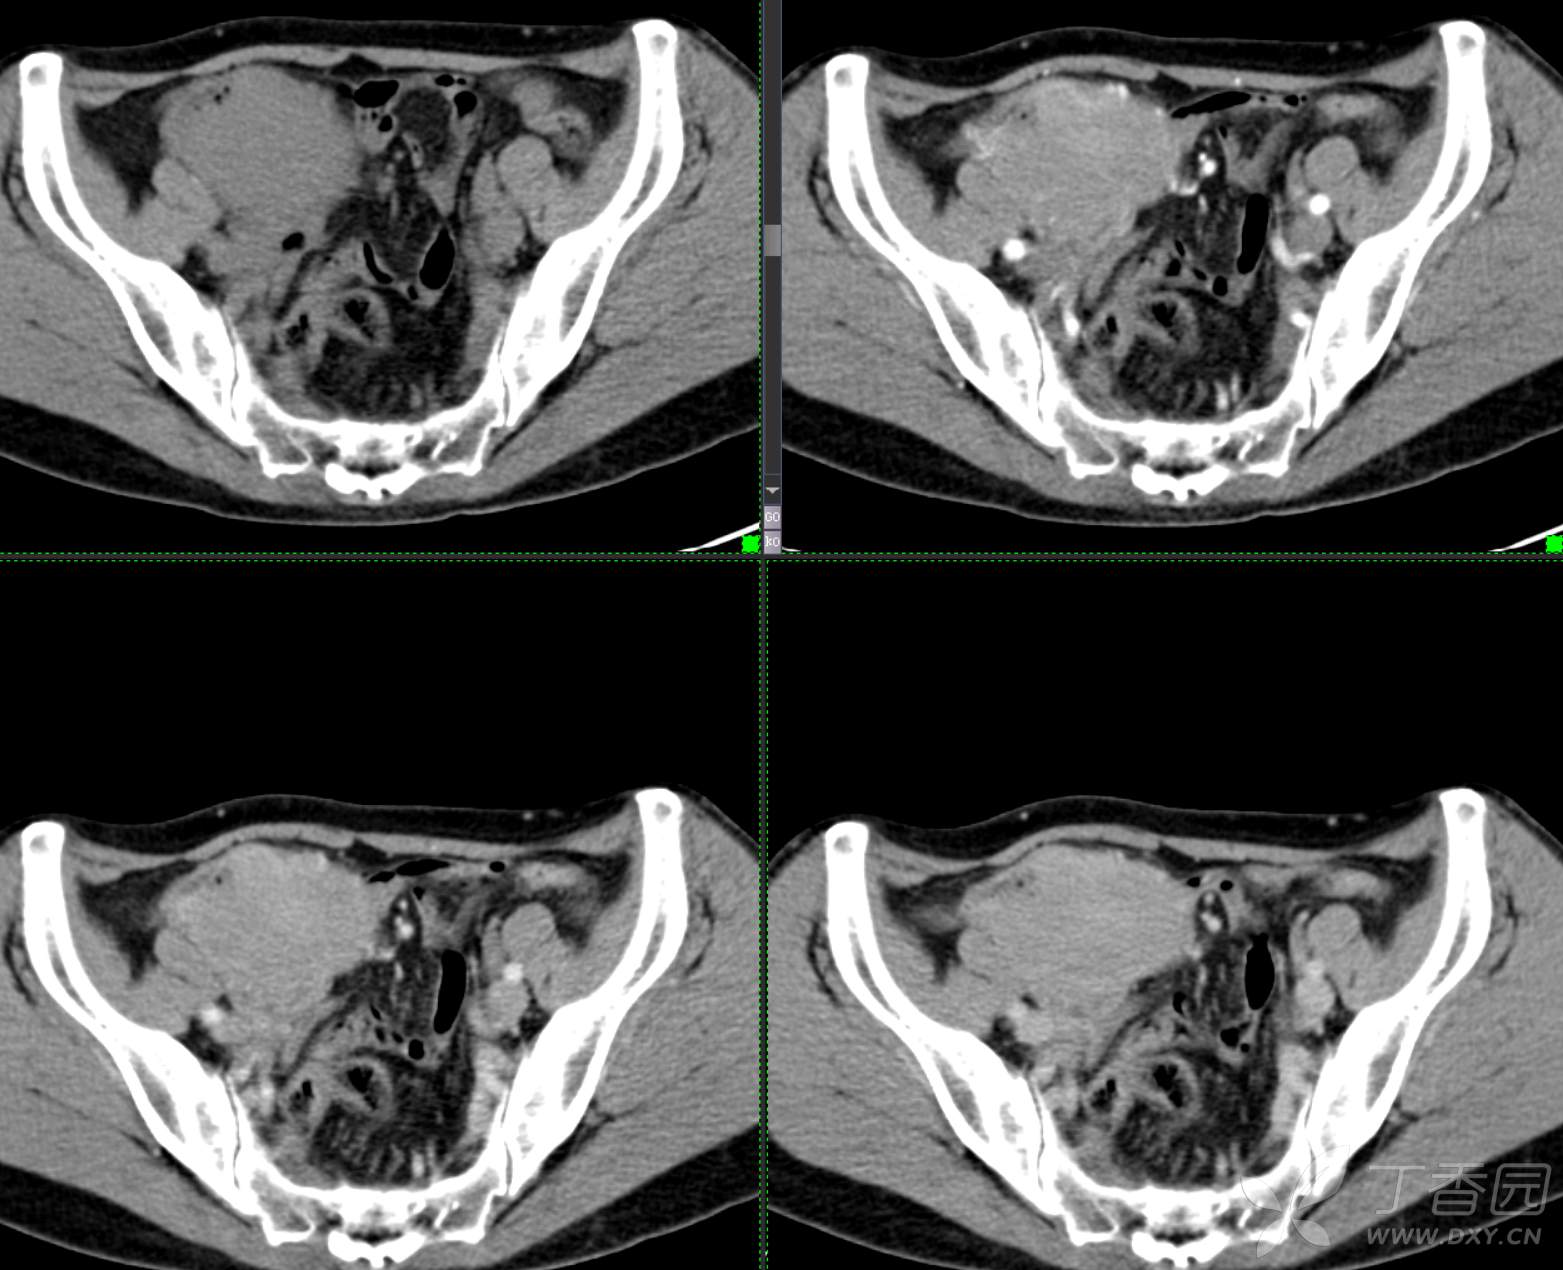

腹组13:患者,女,62岁,大便习惯改变2月余

主 诉: 【大便性状改变2月余】

现病史: 患者2月余前无明显诱因下出现大便次数增多,无明显血便黑便及粘液脓血便,大便次数由1次/日增加至2-3次/日,大便形状变细如小指,偶稀软不成形,无腹痛腹胀腹泻,无恶心呕吐、胸闷气促,肛门排气通畅,无发热盗汗。至当地医院就诊,行肠镜检查发现"回盲部占位"。为进一步治疗,我院门诊拟"回盲部肿瘤"收住入院。